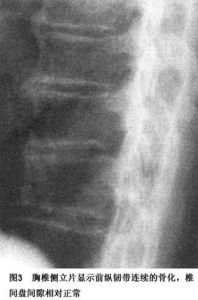

1.胸椎X線表現 胸椎為DISH典型受累區異常鈣化和骨化最常見於胸7~11,上胸椎少見,但也見於胸11~12連續鈣化,骨化者。多見椎體前側方連續的鈣化和骨化,鈣化和骨化呈薄片狀,連續越過椎間隙,範圍較廣泛;當廣泛時在脊柱前側方形成緻密的盾牌狀改變;晚期骨化多凹凸不平特別是在椎間盤水平。

部分椎體上下緣骨贅形成,但椎間盤維持相對高度,骨贅多為刷爪形,並常與椎體前方骨沉積融合往往在椎間盤保持完整的水平骨贅形成最嚴重;韌帶沉積骨與椎體前緣之間出現線狀或半環狀透亮帶,雖然透亮帶不出現在每一個椎體但卻為DISH特徵性的X線改變。此帶經常突然終止於椎體的上緣和下緣,晚期這一透亮帶可隨骨化的進展而消失。

脊椎雙側骨化不對稱,雖常見雙側受累,但胸椎右側好發,左側骨沉積與骨贅少見。